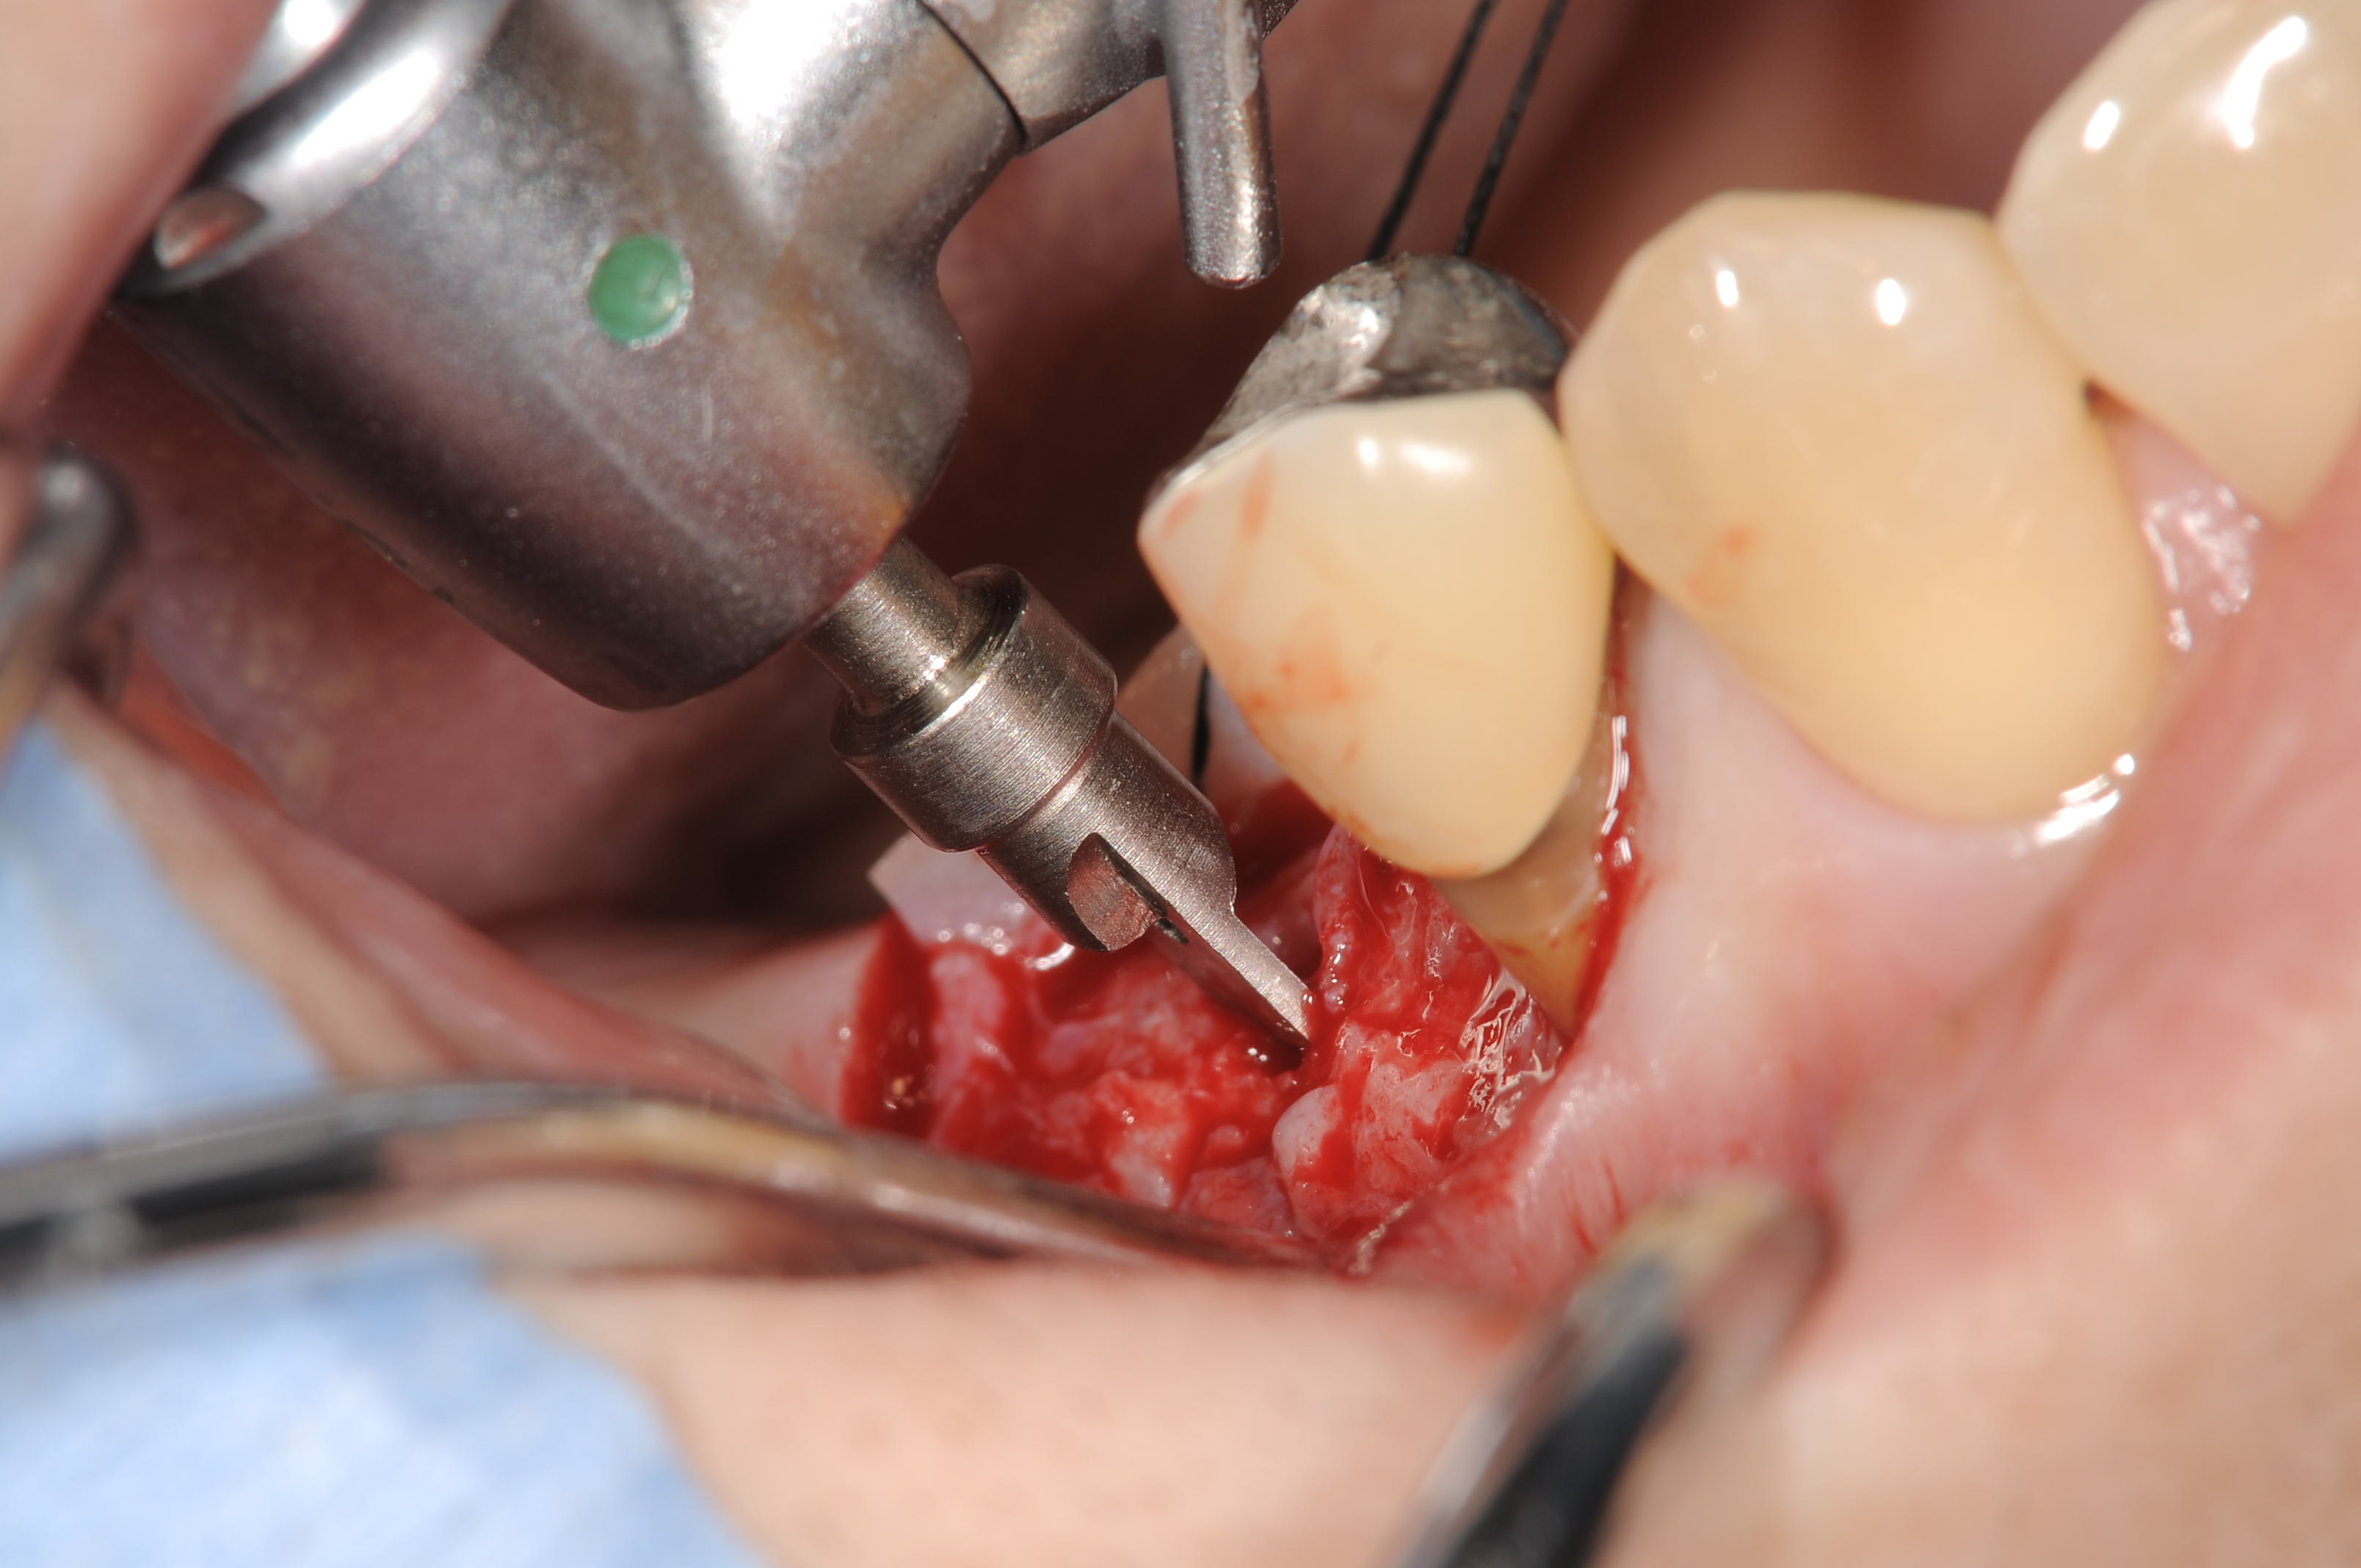

シュナーダー膜を損傷しないように、コッシのバーでドリリングし、オスフェリオンを補てん材としてオステオトームにて膜を挙上しました。

リフティングバーで粘膜を破らないようにドリリングします。

オステオトームテクニックで骨補てん材にオスフェリオンを使用しています。